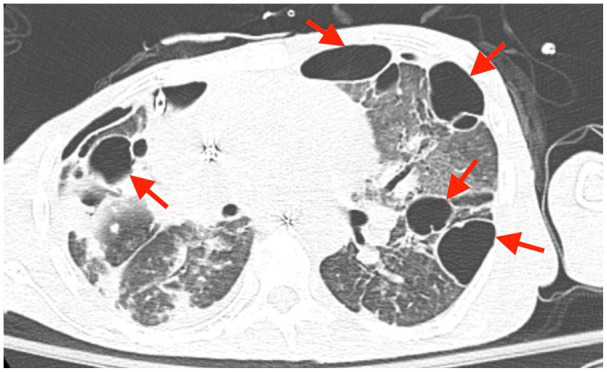

Patients with a history of drug abuse and right-sided endocarditis are particularly susceptible to developing septic pulmonary emboli. Rarely, septic pulmonary emboli can cause severe lung injury resulting in parenchymal loss despite appropriate antibiotic therapy. We present 2 cases of severe lung injury associated with septic pulmonary emboli stemming from right-sided infective endocarditis, emphasizing 2 rare complications: bilateral spontaneous pneumothorax and pneumatocele formation.

Abstract Image